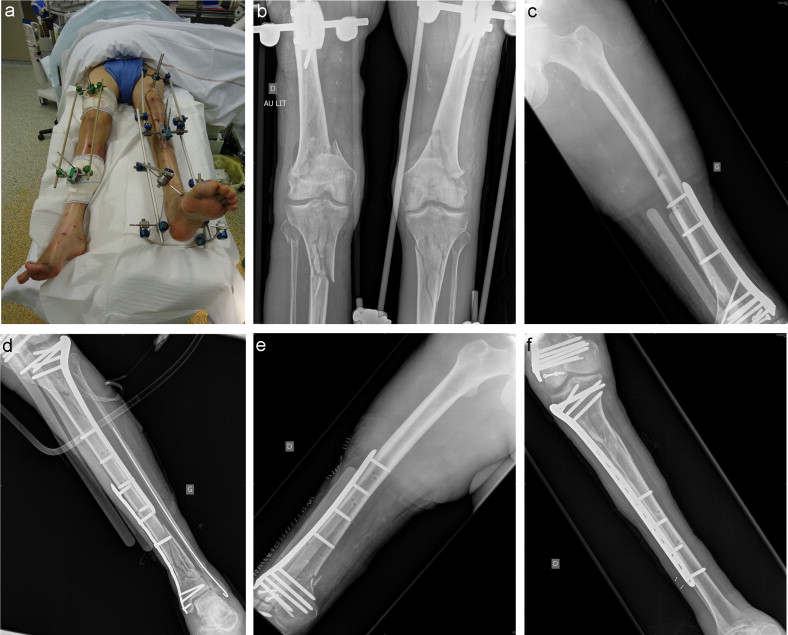

Surgical Approaches and Leg Positions for Tibial Plateau Fractures Gallery Surgical Approaches and Leg Positions for Tibial Plateau Fractures Spinal Cord Injuries Surgical Approaches and Leg Positions for Tibial Plateau Fractures By Pratik|2020-10-22T06:00:37+05:30October 4th, 2020|Spinal Cord Injuries|0 Comments Read More